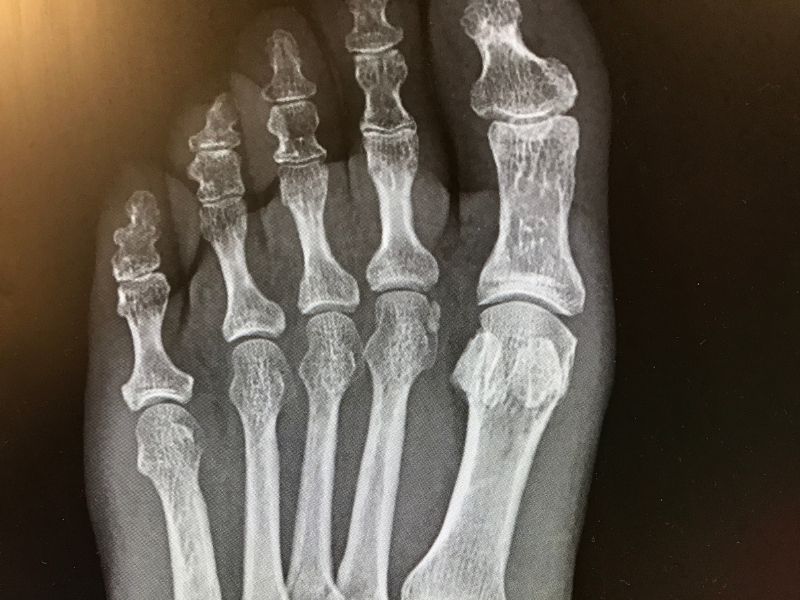

Talus kırığının değerlendirilmesi, kesin tanısının konulması ve nitelik tedavi planlamasının gerçekleştirilebilmesi için birtakım radyolojik tanı araçlarından faydalanılmaktadır.

Bilgisayarlı tomografi ve manyetik rezonans araçları ile talus kırığının derecesi belirlenebilmektedir. Aynı zamanda diyagnostik testler ve röntgen grafilerinden de yararlanılmaktadır.